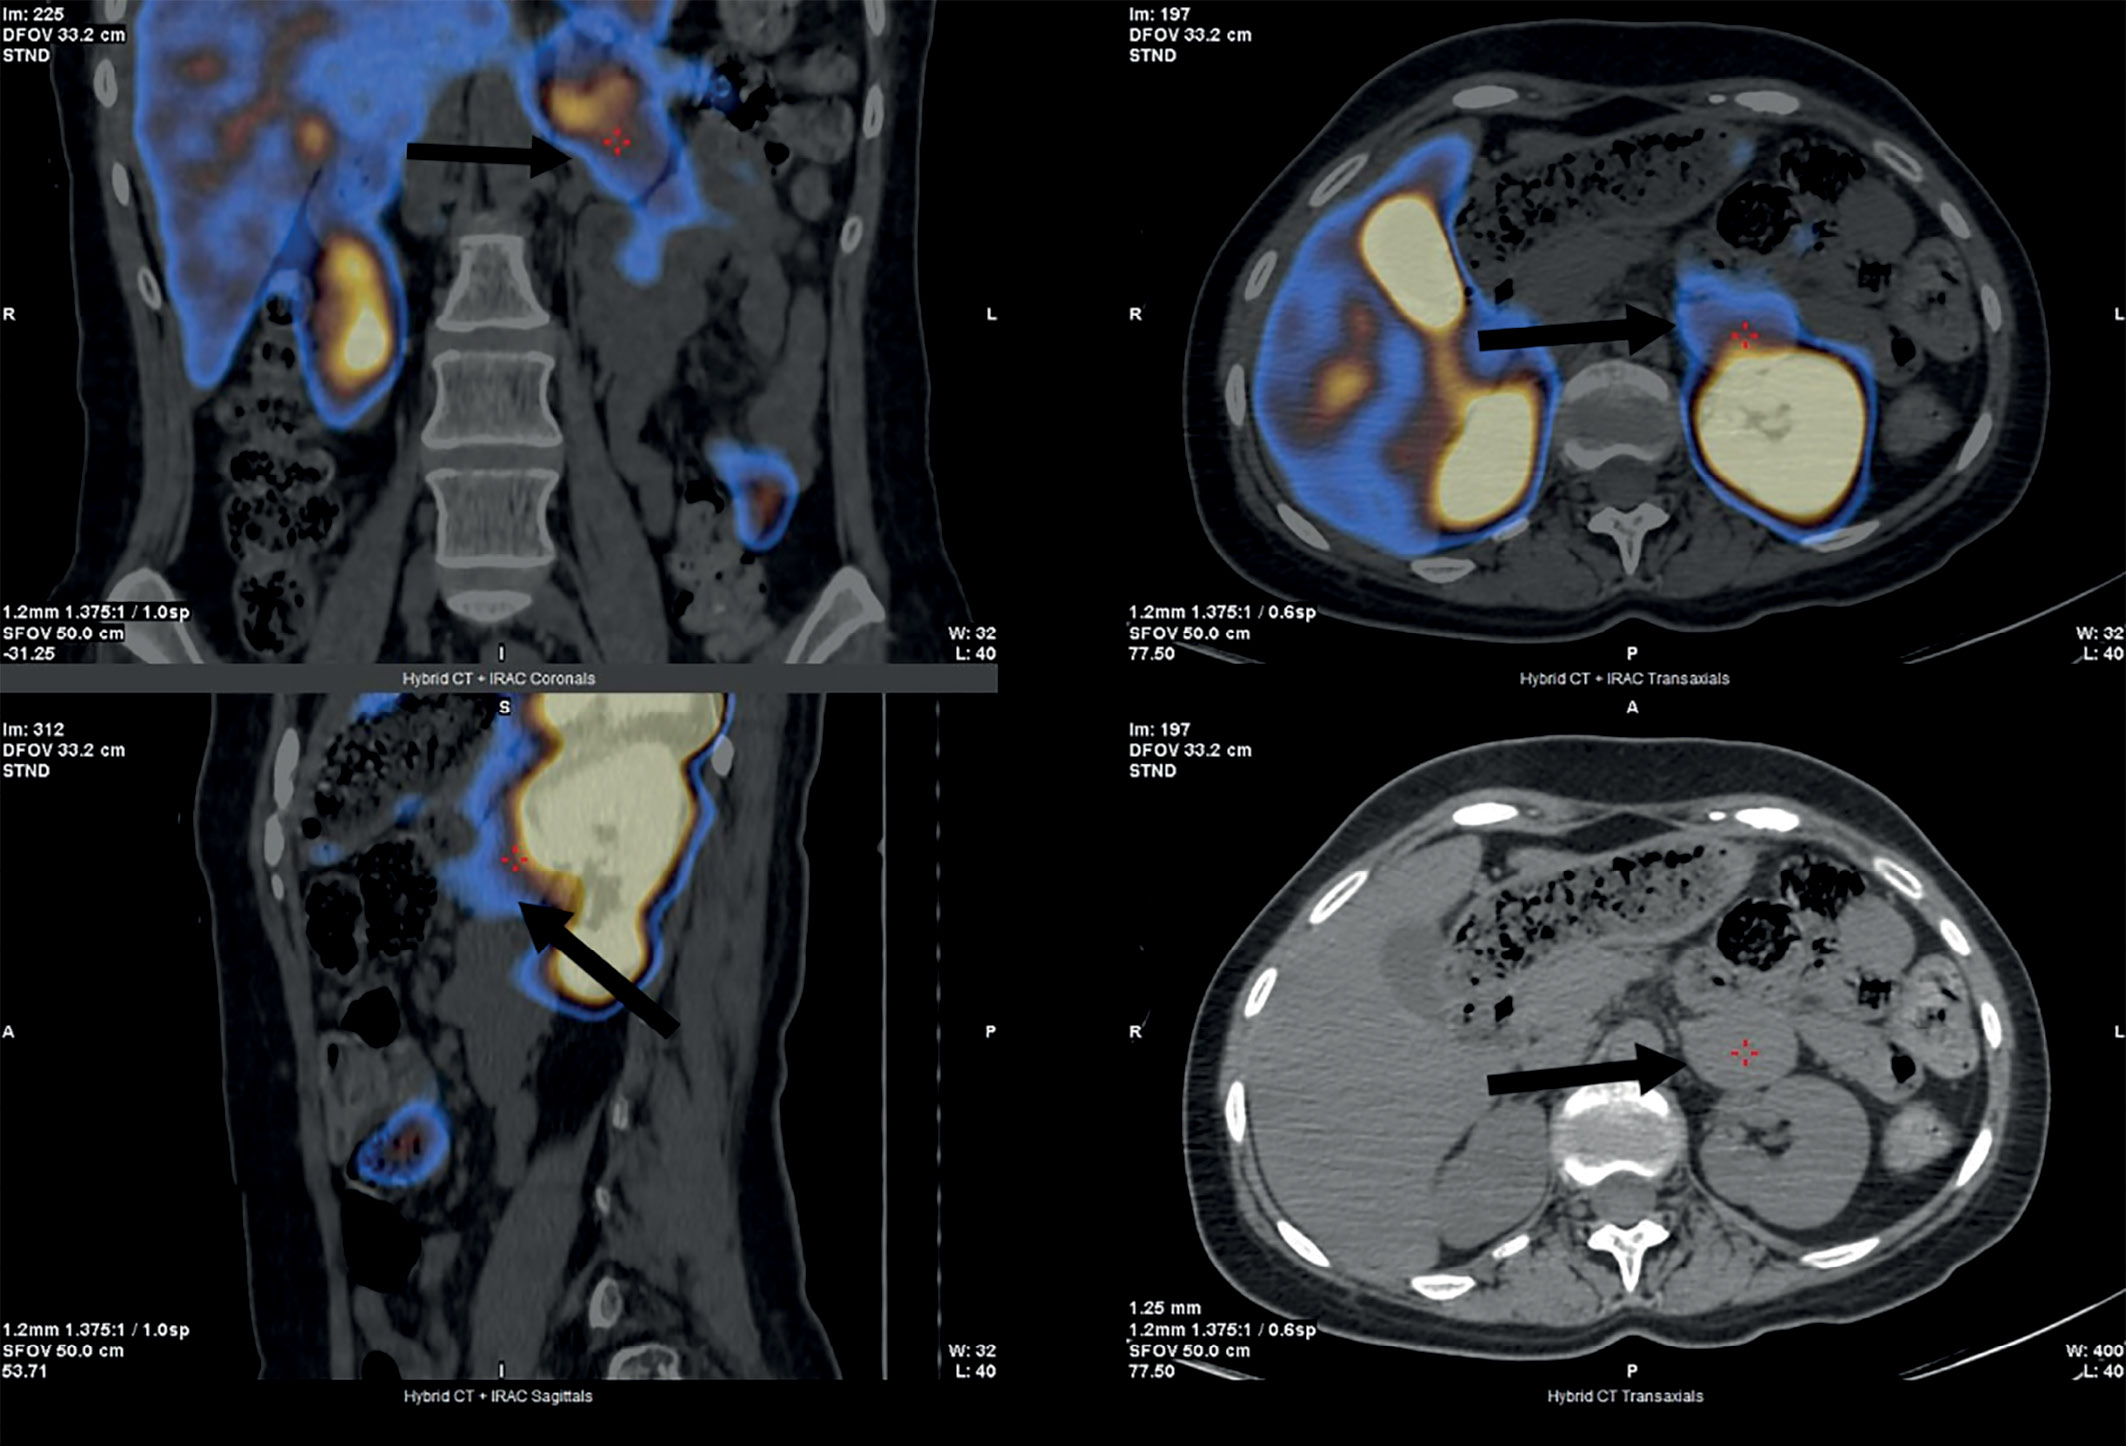

При установке АКТГ-зависимого характера ЭГ для дифференциальной диагностики БИК и АКТГ-эктопированного синдрома проведено МРТ-исследование головного мозга с контрастированием, которое выявило микроаденому задней части аденогипофиза размерами 3х3,5 мм (рис. 1).

Рисунок 1. Магнитно-резонансная томография гипофиза —

стрелками указана микроаденома задней части аденогипофиза.